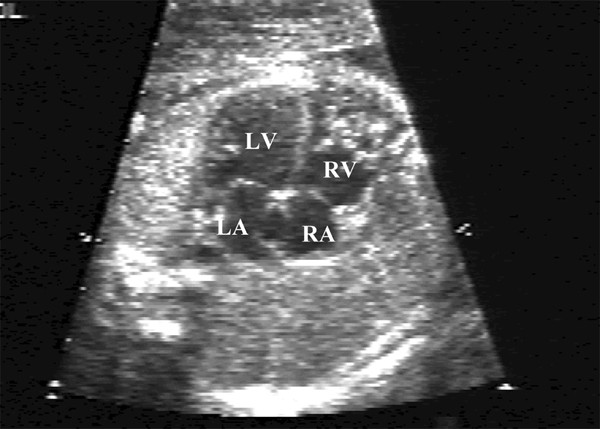

İntrauterin dönemde fetüsün kalp kapakları, çıkış yolları veya ritim sistemine yönelik yapılan invaziv kardiyak girişimlerdir.

1-Kritik Aort Darlığı (Fetal Aortic Stenosis)

Patofizyoloji

- Sol ventrikül çıkışı dar

- LV basınç ↑ → LV hipoplazisi

- Hipoplastik Sol Kalp Sendromu’na gidiş

2-Kritik Pulmoner Darlık / Pulmoner Atrezi (İntakt Septumlu)

Sorun

- Sağ ventrikül çıkışı kapalı/dar

- RV hipoplazisi

- Tek ventrikül riski

3-Hipoplastik Sol Kalp Sendromu’na Gidiş (Borderline HLHS)

- Restriktif foramen ovale